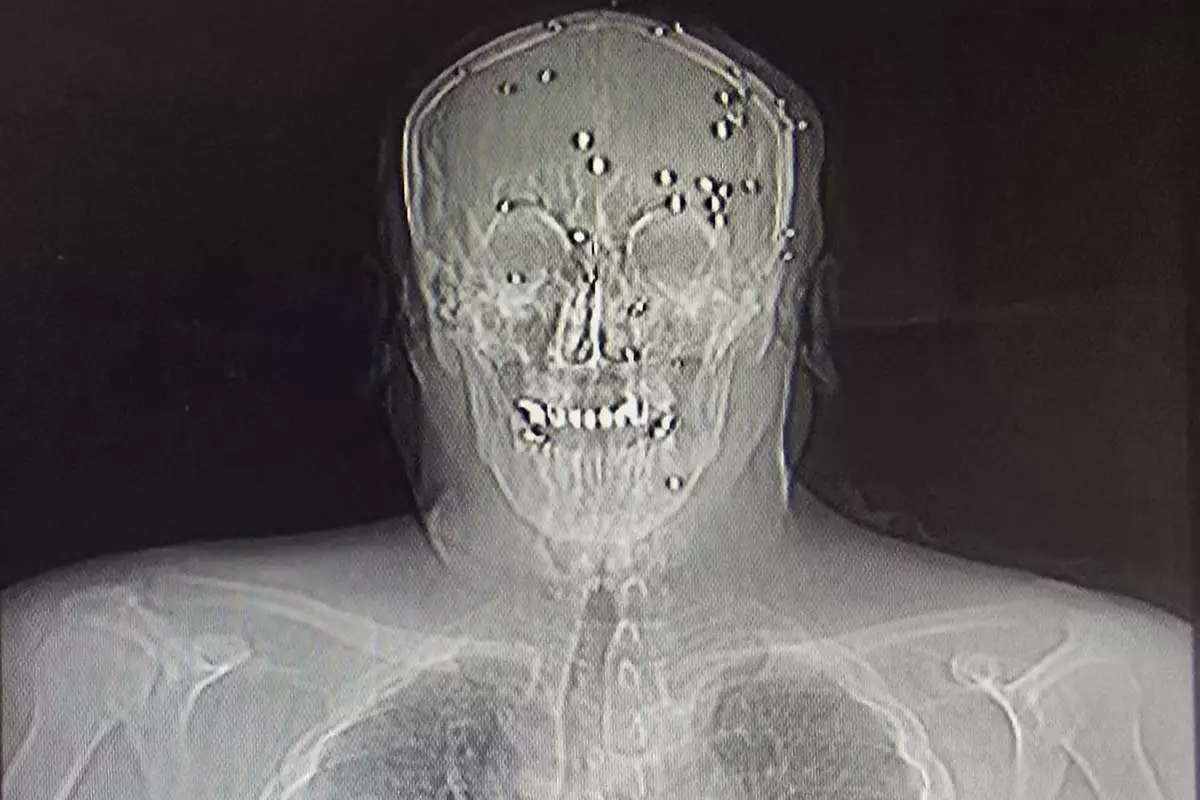

This is a photo of an X-ray image taken Jan. 9, 2026, obtained outside Iran, showing an Iranian protester who was hit in the face by pellets in Rasht, northern Iran. (UGC via AP)